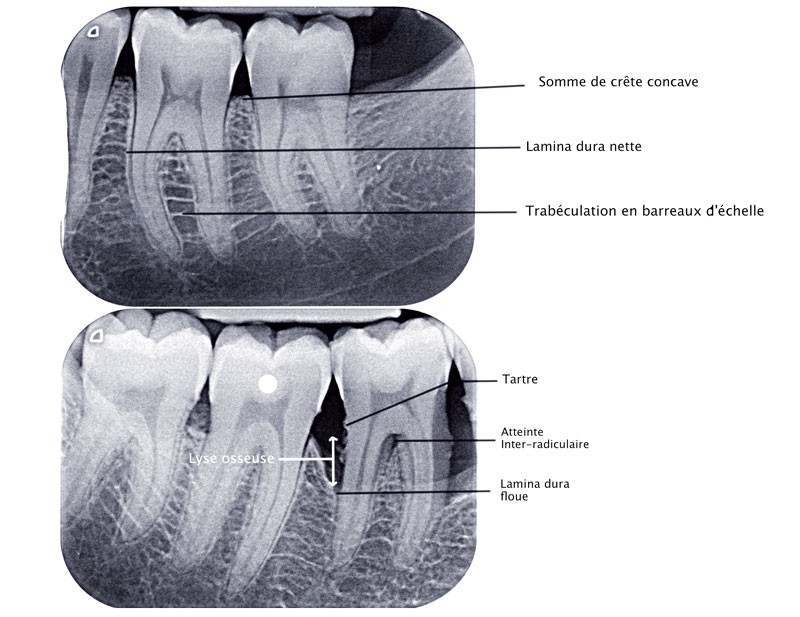

La prise en charge parodontale nécessite un examen clinique rigoureux associant un entretien médical et un bilan parodontal. En complément, la radiologie est utile pour le diagnostic, l’élaboration du plan de traitement et le pronostic de la maladie parodontale. La radiographie panoramique est un premier cliché dit « de débrouillage », mais la réalisation d’un bilan rétroalvéolaire complet est indispensable pour l’analyse des structures dentaires et parodontales profondes. Cet outil permet de suivre la cicatrisation après les premiers traitements et de déceler une récidive pendant les séances de thérapeutique parodontale de soutien. En seconde intention, les nouvelles technologies d’imagerie tridimensionnelle (scanner/cone beam) peuvent être utilisées pour l’exploration de défauts intra-osseux, de lésions inter-radiculaires ou pour planifier une intervention chirurgicale.

Associées à l’examen clinique, les radiographies sont une aide précieuse en parodontologie. Elles orientent le diagnostic, le plan de traitement et le pronostic. Si la radiographie panoramique (ou orthopantomogramme) permet une vue d’ensemble, le bilan rétroalvéolaire reste l’examen privilégié pour l’élaboration d’un diagnostic, d’un plan de traitement et un suivi au long terme. Cependant, ces examens ne sont que des images en 2 dimensions de structures tridimensionnelles et si elles ne sont pas associées à un examen clinique parodontal rigoureux, de nombreuses erreurs peuvent en découler. Les examens 3D ne souffrent pas de la superposition d’éléments anatomiques tridimensionnels mais ne seront utilisés qu’en seconde intention, lorsque l’examen clinique et le bilan rétroalvéolaire n’apportent pas suffisamment de données pour le diagnostic et le plan de traitement (cas particulier de fêlures ou fractures radiculaires, lésions inter-radiculaires, lésions angulaires ou recherche de foyers infectieux…). Par ailleurs, l’exploration radiographique permet de bien connaître la topographie des lésions osseuses (nombre de parois, configuration 3D ….) et permet d’orienter le choix thérapeutique et le pronostic.